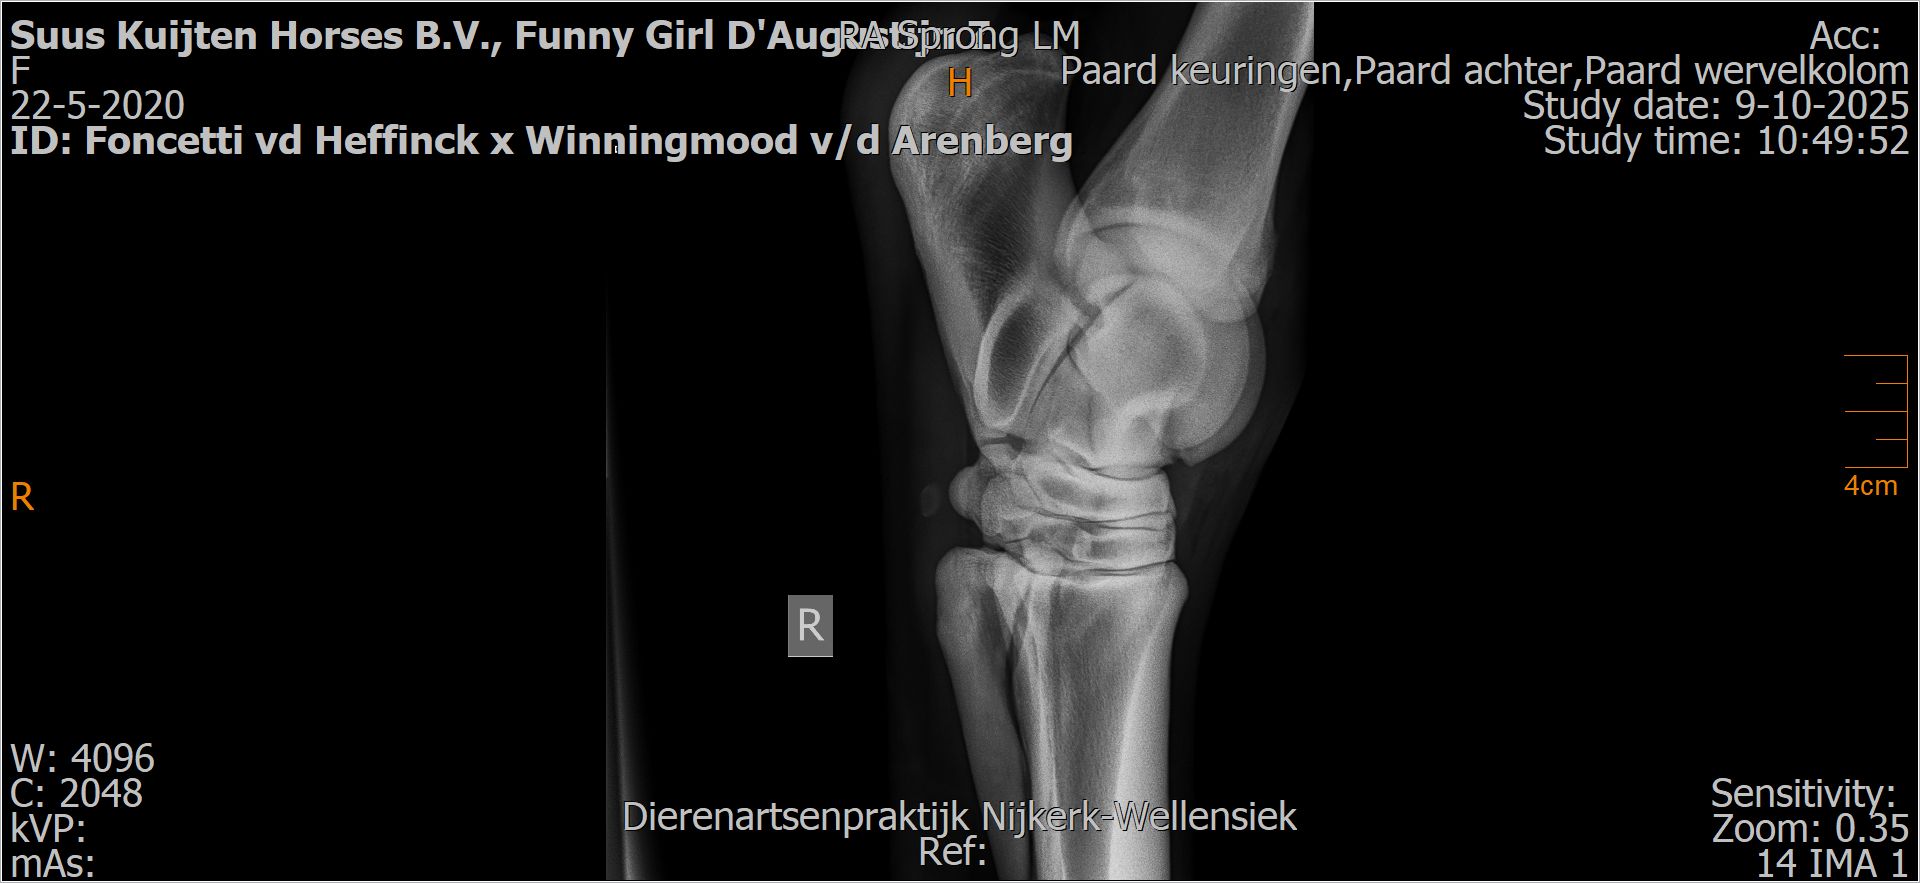

Funny Girl D'Augustijn Z

Röntgenfoto’s